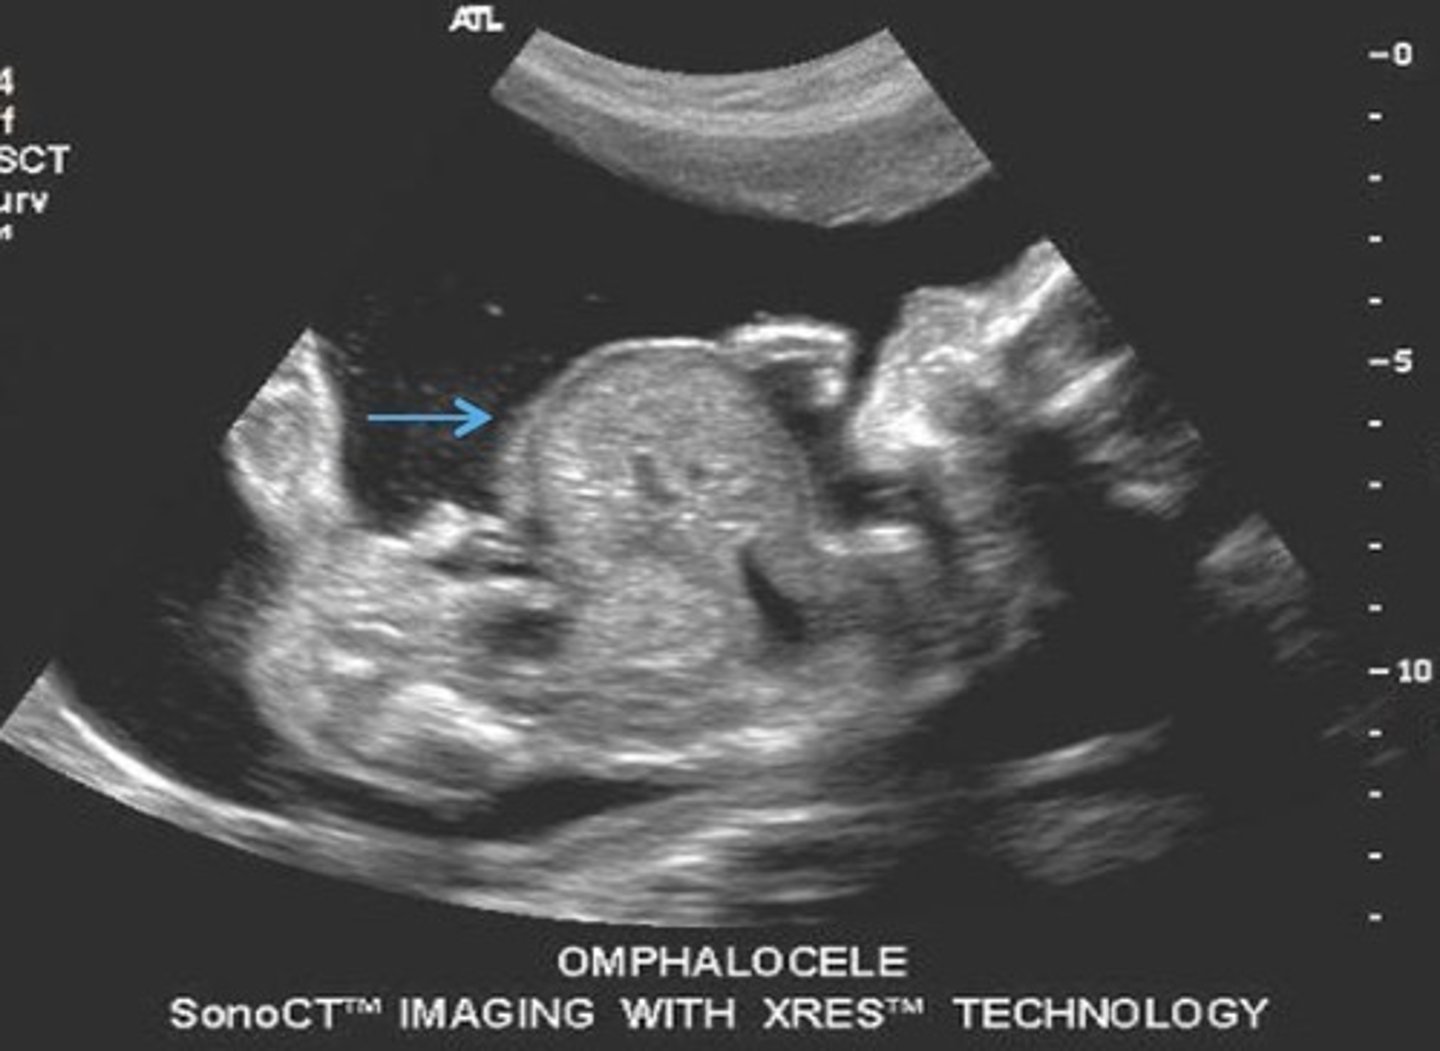

Omphalocele

Herniation of bowel into umbilical cord after 13 weeks

Type 1 Omphalocele

Contains only bowel

80% association with aneuploidy's

Type 2 Omphalocele

Contains bowel and liver

20% association with aneuploidy's